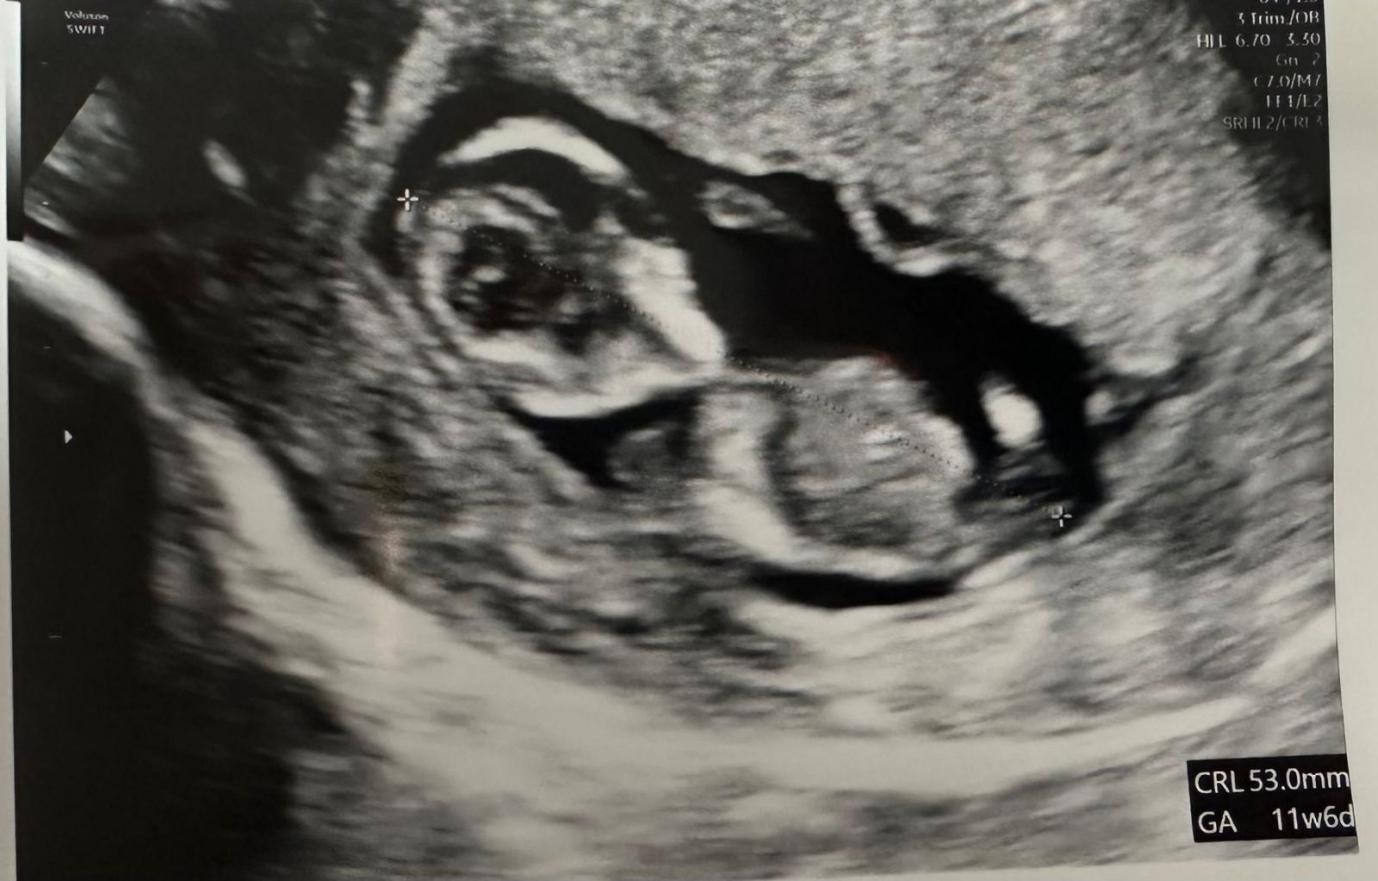

Her abdomen was mildly tender on examination with voluntary guarding. A transvaginal Ultrasound showed a viable intrauterine pregnancy at 12+4 weeks and another viable left tubal ectopic pregnancy of 11 weeks + 6 days gestation. She underwent laparoscopic surgery where a small amount of bleeding was seen in the abdomen, and an ectopic mass in the left adnexa. This mass was removed safely using Ligasure. The procedure was uncomplicated with 100mls of blood loss. She had a bedside USS post-op op which confirmed a viable intrauterinepregnancy.

Figure 1